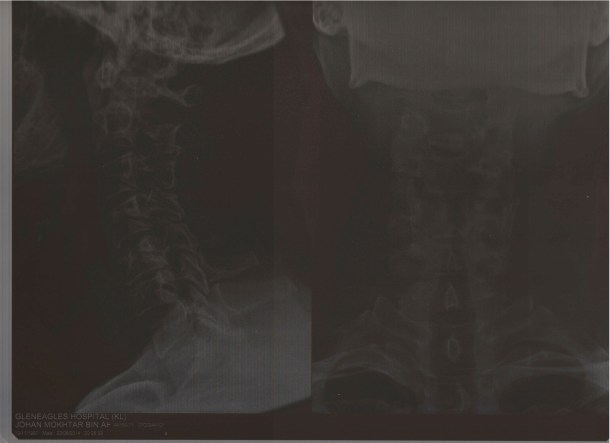

Tuck your head. This is to protect your neck. I must admit this must have been an unconscious reflex. Or I was lucky not to land on my face. My neck is intact, but as you can see from the x-ray of the back of my neck, the vertebrae weren’t exactly in a straight line.